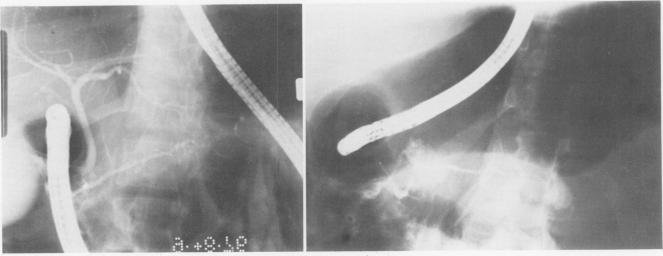

Total or near total pancreatectomy is the surest way to relieve the pain of chronic pancreatitis but is rarely applied because the metabolic consequences are so severe. For most patients drainage procedures are applicable, but pancreatectomy may be the only alternative for small duct disease or where procedures to improve duct drainage have failed. Preservation of endocrine function is a major problem in patients who require pancreatectomy. Experiments in pancreatectomized dogs have shown that intrasplenic or intraportal transplantation of unpurified pancreatic islet tissue dispersed by collagenase digestion can prevent diabetes. We have applied this technique to ten patients with chronic pancreatitis, small ducts, and intractable pain. The entire pancreas of > 95% of the pancrease was excised, minced, dispersed by collagenase digestion and infused into the portal vein < 2 1/2 hours after removal. Mean (+/- SD) rise in portal pressure was 17 +/- 8 cm of water. Liver function tests were altered minimally. All patients were relieved of pain. One patient died of a complication not related to the islet autotransplant; viable islets were identified in the liver at autopsy. Of the remaining nine patients, three have been insulin independent for 1, 9, and 38 months. One patient was insulin indpendent for 15 months and now takes 12 units of insulin daily. Three have nonketosis prone diabetes (tested by insulin withdrawal) and take 15--30 units of insulin per day. C-peptide studies in these patients show that functioning islets are present. Two patients are diabetic and require 35 and 60 units of insulin per day. In eight of nine patients tested serum insulin concentrations fell to undetectable levels during the interval between pancreatectomy and islet transplantation. Serum insulin levels during the first few hours after islet transplantation predicted success. In the insulin independent or in the patients with mild diabetes, insulin levels were persistently greater than or equal to 6 microU/ml. In the other two patients, the increase in insulin concentration was not sustained. Islet tissue preparation from a diseased pancreas is difficult. The surgeon and the patient must still be willing to accept diabetes for relief of pain when performing this operation. In some patients, however, islet autotransplantation can prevent or partially ameliorate diabetes after pancreatectomy, and preservation of endocrine function is worthwhile.

全胰切除术或近全胰切除术是缓解慢性胰腺炎疼痛最可靠的方法,但很少应用,因为其代谢后果非常严重。对于大多数患者而言,引流手术是可行的,但对于小导管疾病或改善导管引流的手术失败的情况,胰切除术可能是唯一的选择。对于需要进行胰切除术的患者,保留内分泌功能是一个主要问题。对胰腺切除的狗进行的实验表明,通过胶原酶消化分散的未纯化胰岛组织进行脾内或门静脉内移植可以预防糖尿病。我们已将此技术应用于10例患有慢性胰腺炎、小导管和顽固性疼痛的患者。切除了超过95%的胰腺,切碎,经胶原酶消化分散,并在切除后不到2个半小时内注入门静脉。门静脉压力平均(±标准差)升高17±8厘米水柱。肝功能检查仅有轻微改变。所有患者的疼痛均得到缓解。1例患者死于与胰岛自体移植无关的并发症;尸检时在肝脏中发现了存活的胰岛。其余9例患者中,3例已分别在1个月、9个月和38个月内无需胰岛素治疗。1例患者曾在15个月内无需胰岛素治疗,现在每天注射12单位胰岛素。3例有非酮症倾向糖尿病(通过停用胰岛素检测),每天注射15 - 30单位胰岛素。对这些患者进行的C肽研究表明存在有功能的胰岛。2例患者患有糖尿病,每天需要35和60单位胰岛素。在接受检测的9例患者中的8例中,血清胰岛素浓度在胰切除术和胰岛移植之间的间隔期降至无法检测的水平。胰岛移植后最初几个小时的血清胰岛素水平可预测手术是否成功。在无需胰岛素治疗或患有轻度糖尿病的患者中,胰岛素水平持续大于或等于6微单位/毫升。在另外2例患者中,胰岛素浓度的升高未持续。从患病胰腺制备胰岛组织很困难。在进行此手术时,外科医生和患者仍必须愿意接受糖尿病以缓解疼痛。然而,在一些患者中,胰岛自体移植可以预防或部分改善胰切除术后的糖尿病,并且保留内分泌功能是值得的。